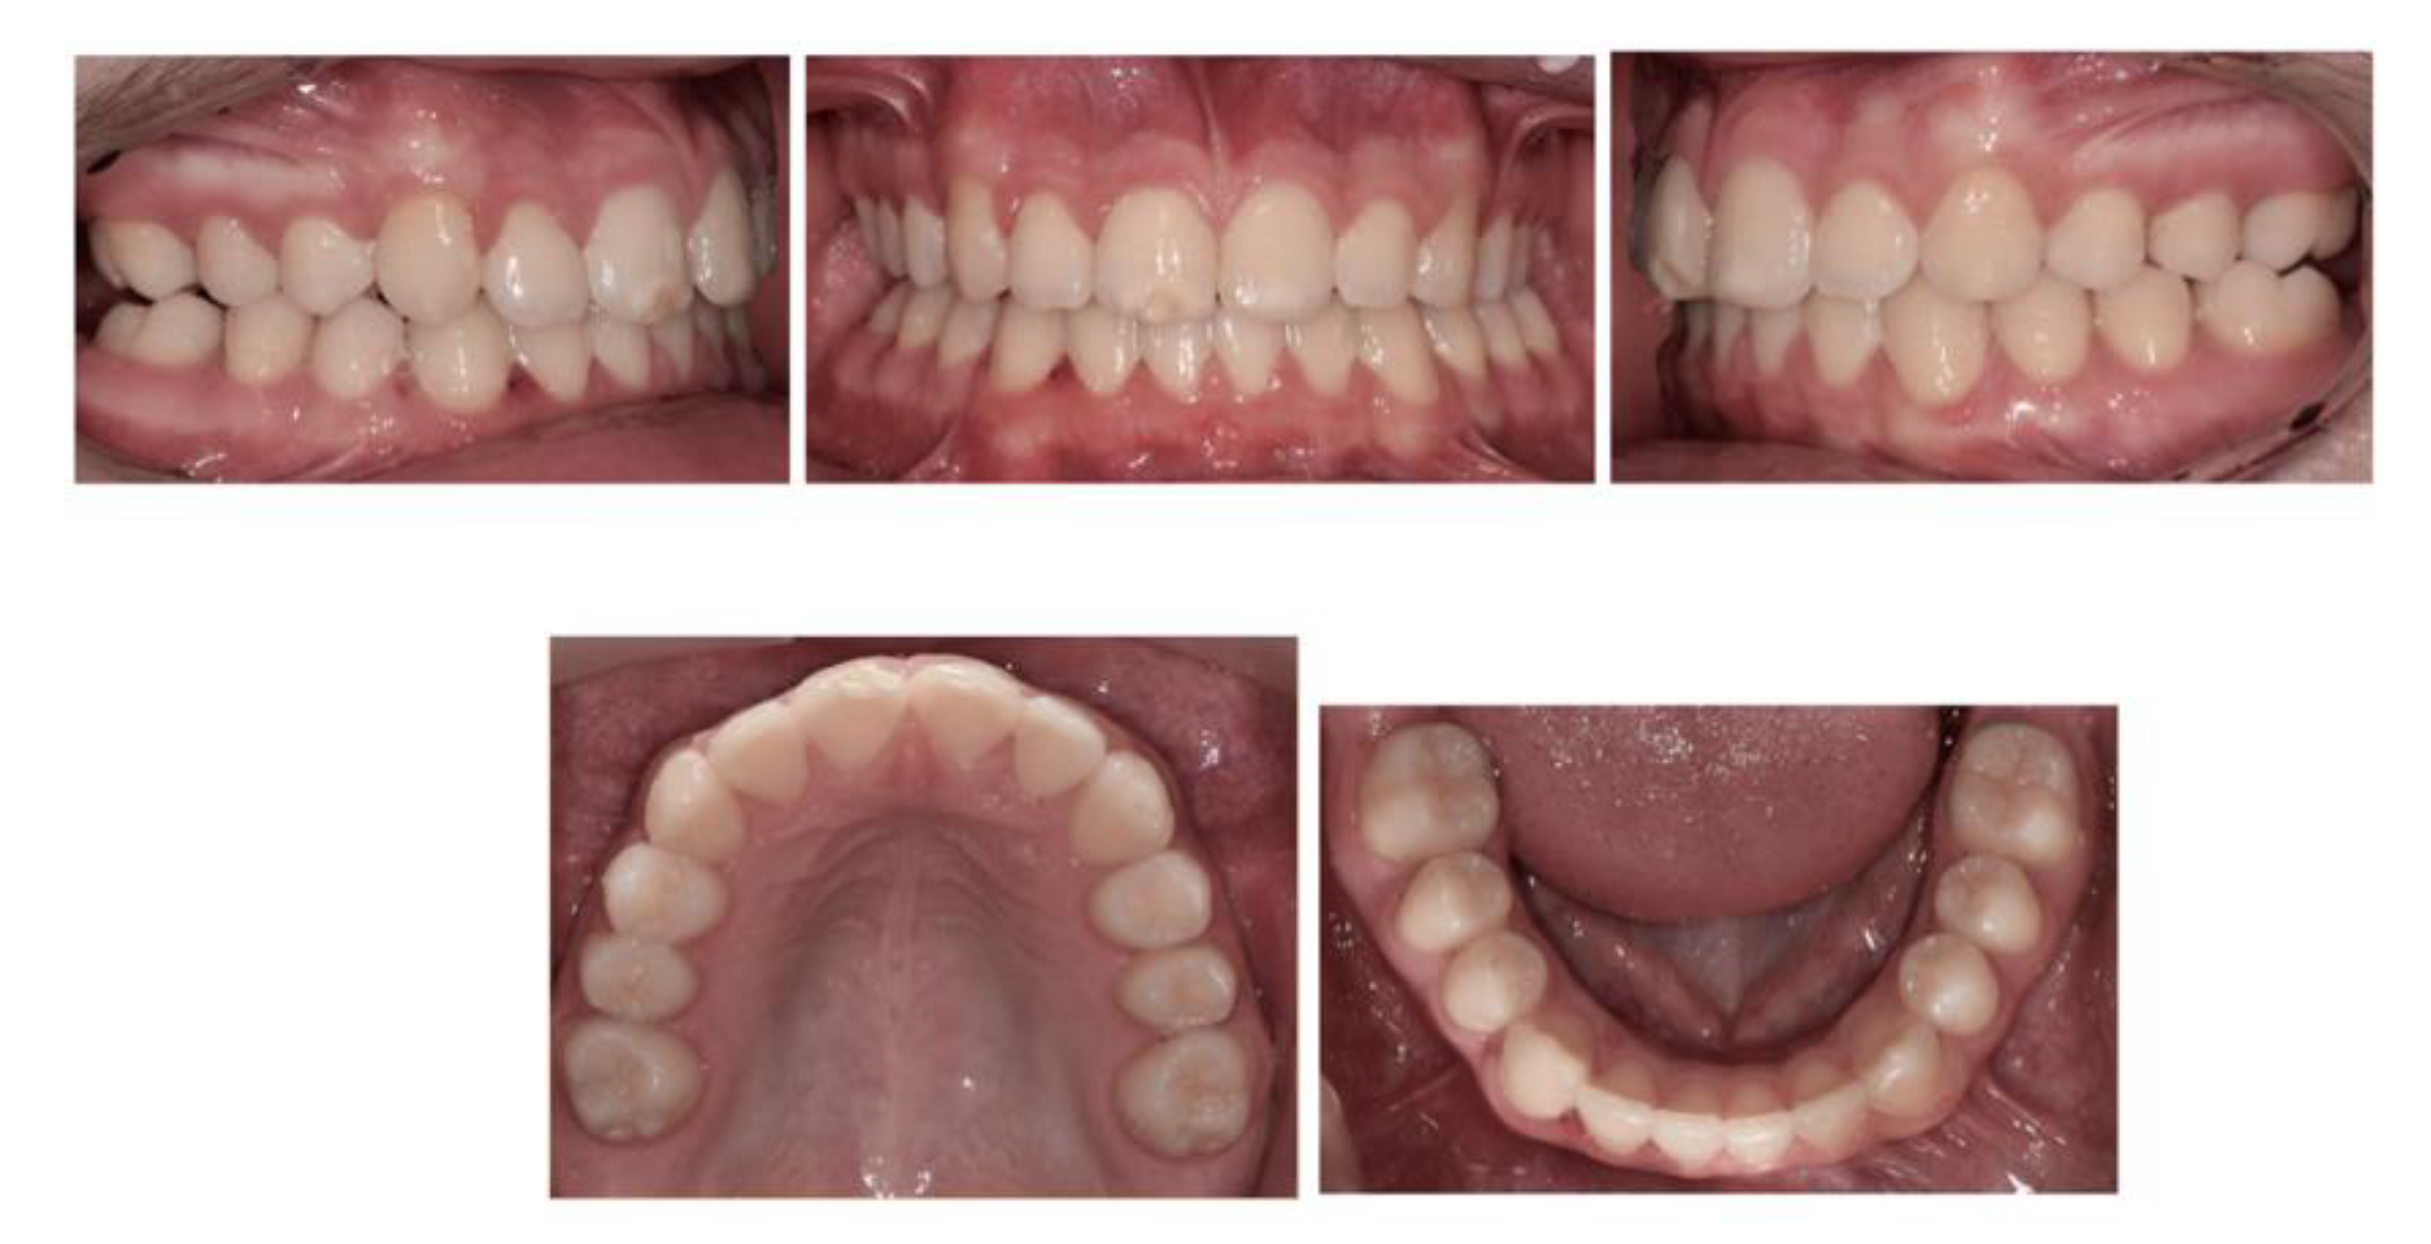

2.1. Case 1—Delayed Extraction of FPMs

Discussion

2.2. Case 2—Timely Extraction of FPMs